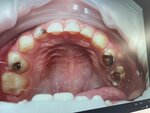

Dental clinic Da Vinci, Khabarovsk, photo